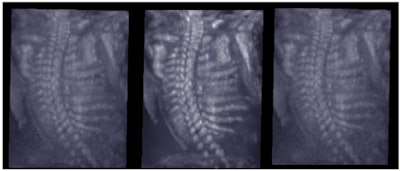

With 3D ultrasound, organs and deep embedded structures become visible with their true geographic position and orientation. The clinical benefits are substantial and will allow clinicians the opportunity to acquire more accurate information faster. Tutschek stated that "volume 3D enables ideal examination setting and correlation of every point in the two or three orthogonal planes."2

![]() |

| 3D-acquired fetal spine image, rendered view. To the left is the nonprocessed original, in the middle is the 3D image-enhanced spine, and to the right is the respective 2D-enhanced image. Note the clear delineation of the fetal spine in the 3D-enhanced image. Images courtesy of Dr. Anders Selbing, PhD.1 |